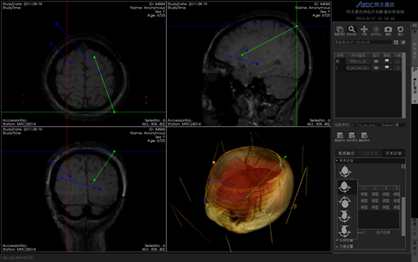

同方鼎欣專業(yè)影像產(chǎn)品群是直接面向神經(jīng)外科、骨科、血管分析等臨床科室的輔助診療、手術(shù)計劃、分析的解決方案,系統(tǒng)整合了醫(yī)療影像的導入、二維閱片、三維重建、序列配準融合、自動分割、自動計算、手術(shù)計劃等一系列功能。充分滿足了臨床科室的專業(yè)需求,提供了完整、強大、可靠、方便的工具平臺。